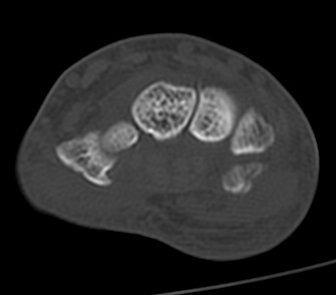

ÄÄÇ»ÅÍ ÃÔ¿µ :  Äá¾Ë»À ºÐ¼â°ñÀýÀÌ °üÂûµÊ(»çÁø 7, 8, 9, 10).